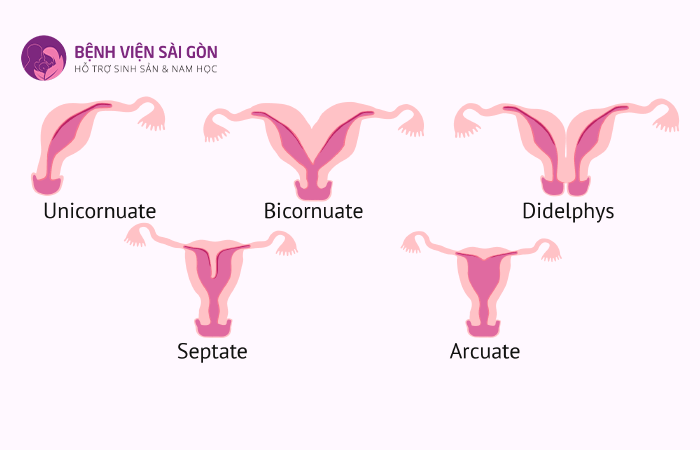

3. Tử cung dị dạng có bao nhiêu loại

Người bệnh có tử cung dị dạng thì hình thái sẽ là một trong những dạng dưới đây. Việc xác định hình thái tử cung bất thường sẽ giúp các chuyên gia dễ dàng tìm ra cách điều trị phù hợp và hiệu quả cho từng đối tượng.

3.3 Tử cung một sừng

Loại dị dạng này chỉ có một buồng trứng và một ống dẫn trứng trong tử cung nên khó mang thai hơn.

3.4 Tử cung hai sừng

Đặc điểm của loại tử cung dị dạng này là có hai phần tách biệt nhưng chỉ có một cổ tử cung kết nối với lớp nội mạc và kéo dài đến cổ tử cung khiến chúng có 2 sừng hoàn toàn hoặc một phần.